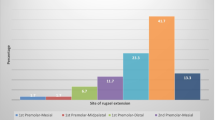

Major- and secondary branches of the GPA and its relation to the palatine spine, different anastomoses with NPA and LPA as well as with contralateral branches of the GPA were recorded (Figs. 1 and 2). Another important record of patients with an edentulous upper jaw revealed that due to the resorption of the bone, the GPA developed a curvy pathway especially at the area of the molars-premolars (Fig. 3). Also, some penetrating intraosseous branches at the premolar-canine area were observed (Fig. 4). The blood supply around the maxillary tuberosity was also presented. As soon as the greater palatine artery emerges out from the greater palatine foramen, it sends one to two branches toward the tuberosity and also the lesser palatine artery sends one to two branches forming anastomoses at this area (Fig. 5). The abovementioned findings are summarized in Fig. 6, which clearly demonstrates the complexity of palatal blood supply.

At the level of the second molars, the distance of the GPA branches from the level of the crestal bone was 11.3 ± 0.9 mm on average (ranging 10–13 mm). In all the cadavers, high amount of adipose and dense connective tissues were detected together with numerous vessels. In those cadavers showing signs of obesity, increased amount of adipose tissue was observed in the posterior palate compared to cadavers without signs of obesity. Uniform distribution and pathway of anatomical landmarks was observed in all cadavers, no discrepancies were found except for differences related to edentulous/dentate condition of the cadavers.

A study by Reiser et al. [20] suggested that the greater palatine neurovascular bundle lies 17 mm from the gingival margin in patients with high palatal vault, and 12 mm from the gingival margin in patients with medium palatal vault, while in patients with low palatal vault the distance was 7 mm. According to our present findings, in edentulous cadavers due to the resorption of the alveolar ridge, the area for the pathway of the GPA might decrease in apico-coronal and oro-vestibular dimension and the GPA would exhibit a more undulating pathway. We were able to demonstrate that in edentulous cases the GPA with its subbranches became more superficial, which might increase the risk of GPA injury during any type of palatal flap preparation, e.g., connective tissue graft harvesting or during augmentation procedures. Due to this specific curvy outline of arteries, the distance of the GPA from the crest was reduced by 3–4 mm, thus increasing the risk for arterial injury during connective tissue harvesting. Therefore, at edentulous sites, superficial removal of a FGG can be a more secure clinical procedure for connective tissue harvesting as opposed to the single incision or trapdoor techniques.